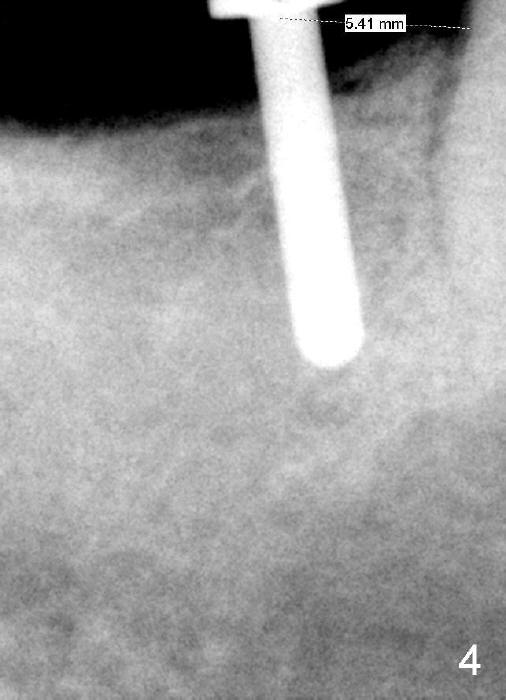

A 57-year-old lady returns for #31 implantation. The vertical edentulous space is limited, as the opposing tooth is supraerupted (Fig.1 arrow). Preop PA is critical (Fig.2), since it is used to measure the bone height (Fig.3: 12 mm). The length of the implant is expected to be 10 mm. The initial osteotomy depth is 8 mm (Fig.4); it appears that the trajectory should be adjusted. Osteotomy increases following depth and angulation adjustment (Fig.5: 4.5x10 mm drill). The submerged implant (5.3x10 mm) is placed with insertion torque approximately 35 Ncm (Fig.6). The buccal microthreads are exposed (Fig.7); to prepare for bone graft, the buccal plate is decorticated. Following placement of freeze dry mineralized allograft, collagen membrane is fixated by a healing screw (Fig.8). The incision is closed by 4-0 Chromic gut sutures and perio glue (Fig.9).